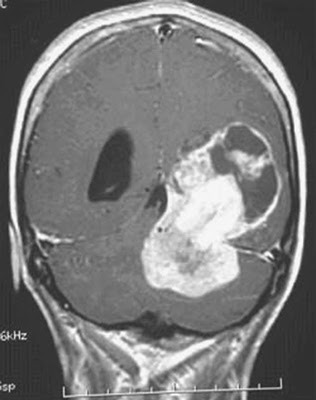

For the past two days,I wrote a story in two parts,using myself as the main character.We Will See What Happens To Me Tomorrowwas part one written onMondayandWe Will See What Happens To Me Todaywas part two written yesterday,Tuesday December 20th.In the story I mention that I have been diagnosed with having an inoperable brain tumor.I used an actualCT Scanof someone with a tumor inside his skull.For some reason,this started real concern about my health.Generating a few phone calls from people who are dear to me,including myWife.I won't tell you what she said to me,by withholding this kind of information from her,because thisBlogis ratedPG-13.

I don't have aCT Scanwith the same angle as theX-rayabove,but I did have one taken of me last month,proving there is no tumor inside my brain,but that I am missing a couple of molars.

I don't have aCT Scanwith the same angle as theX-rayabove,but I did have one taken of me last month,proving there is no tumor inside my brain,but that I am missing a couple of molars.

You can plainly see I have a sound mind but that I have to have teeth implants put into my mouth.I am now accepting donations for a charitable cause called,"Keep Jim Beautiful."Any amount will be accepted.Before I get myself into more trouble by soliciting funds,I am kidding!I wouldn't compare my little scare to that ofOrsen Welles's1938 radio broadcast of"The War of the Worlds,"where part of the country panicked,believing there was a real alien invasion happening.But,I did cause enough of a stir among familyand friends that I had to write this detraction."I do not have a brain tumor. I have a brain deficiency in not informing people that it was just a story."Thank you though for caring.If you do not know whoOrsen Wellesis,I suggest you rent a few films he either starred inor directed.As far as making films inHollywood,he was a genius.This is,I Kind Of Enjoyed Stirring Up People And Having Them Call Me To See If I Was OK,Jim Hauenstein,

You can plainly see I have a sound mind but that I have to have teeth implants put into my mouth.I am now accepting donations for a charitable cause called,"Keep Jim Beautiful."Any amount will be accepted.Before I get myself into more trouble by soliciting funds,I am kidding!I wouldn't compare my little scare to that ofOrsen Welles's1938 radio broadcast of"The War of the Worlds,"where part of the country panicked,believing there was a real alien invasion happening.But,I did cause enough of a stir among familyand friends that I had to write this detraction."I do not have a brain tumor. I have a brain deficiency in not informing people that it was just a story."Thank you though for caring.If you do not know whoOrsen Wellesis,I suggest you rent a few films he either starred inor directed.As far as making films inHollywood,he was a genius.This is,I Kind Of Enjoyed Stirring Up People And Having Them Call Me To See If I Was OK,Jim Hauenstein,

I don't have aCT Scanwith the same angle as theX-rayabove,but I did have one taken of me last month,proving there is no tumor inside my brain,but that I am missing a couple of molars.

I don't have aCT Scanwith the same angle as theX-rayabove,but I did have one taken of me last month,proving there is no tumor inside my brain,but that I am missing a couple of molars.

You can plainly see I have a sound mind but that I have to have teeth implants put into my mouth.I am now accepting donations for a charitable cause called,"Keep Jim Beautiful."Any amount will be accepted.Before I get myself into more trouble by soliciting funds,I am kidding!I wouldn't compare my little scare to that ofOrsen Welles's1938 radio broadcast of"The War of the Worlds,"where part of the country panicked,believing there was a real alien invasion happening.But,I did cause enough of a stir among familyand friends that I had to write this detraction."I do not have a brain tumor. I have a brain deficiency in not informing people that it was just a story."Thank you though for caring.If you do not know whoOrsen Wellesis,I suggest you rent a few films he either starred inor directed.As far as making films inHollywood,he was a genius.This is,I Kind Of Enjoyed Stirring Up People And Having Them Call Me To See If I Was OK,Jim Hauenstein,

You can plainly see I have a sound mind but that I have to have teeth implants put into my mouth.I am now accepting donations for a charitable cause called,"Keep Jim Beautiful."Any amount will be accepted.Before I get myself into more trouble by soliciting funds,I am kidding!I wouldn't compare my little scare to that ofOrsen Welles's1938 radio broadcast of"The War of the Worlds,"where part of the country panicked,believing there was a real alien invasion happening.But,I did cause enough of a stir among familyand friends that I had to write this detraction."I do not have a brain tumor. I have a brain deficiency in not informing people that it was just a story."Thank you though for caring.If you do not know whoOrsen Wellesis,I suggest you rent a few films he either starred inor directed.As far as making films inHollywood,he was a genius.This is,I Kind Of Enjoyed Stirring Up People And Having Them Call Me To See If I Was OK,Jim Hauenstein,And,